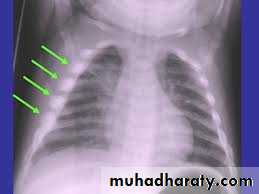

أشعة الصدر لطفل معذب، لاحظ الكسور المتسلسلة في الاضلاع

كسور الأجزاء الخلفية من الأضلاع